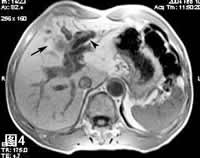

图4: MRI、T1WI,示肝左叶肿瘤与肝实质近等信号强度(箭号),远侧肝内扩张的肝管内呈低信号。